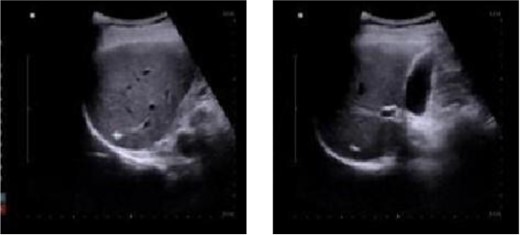

The patient received anti-infective therapy comprising imipenem and cilastatin sodium along with a high-calorie digestible diet. By the sixth day post-surgery, the patient exhibited normothermia, improved appetite, and alleviation of abdominal discomfort. Subsequent routine blood analysis revealed a white blood cell count of 11.79 × 10^9/L, lymphocyte percentage of 21.3%, and neutrophil percentage of 70.7%. Re-evaluation using abdominal color ultrasound on postoperative Day 12 revealed that the extent of the abscess in the right hepatic lobe was reduced to 24 mm × 19 mm (Fig. 2).

Abdominal color ultrasound findings on the 12th day after surgery.